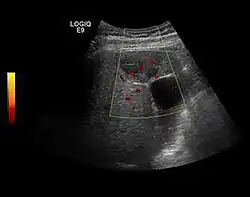

The ultrasound appearance is a well defined lesion, with very thin, almost unapparent walls, without circulatory signal at Doppler or CEUS investigation. The content is transonic suggesting fluid composition. The presence of membranes, abundant sediment or cysts inside is suggestive for parasitic, hydatid nature. Posterior from the lesion the acoustic enhancement phenomenon is seen, which strengthens the suspicion of fluid mass. They typically displace normal liver vessels but no vascular or biliary invasion occurs.

Hydatid liver cyst. Diagnostic criteria are the presence of membranes and sediment inside.